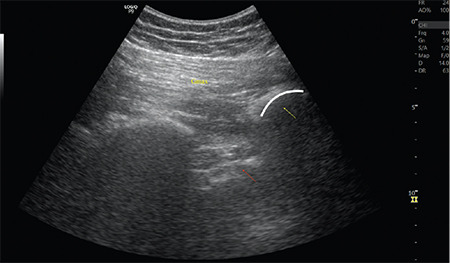

Facioscapulohumeral muscular dystrophy (FSHD) is a muscular dystrophy that can affect individuals of all age groups. Its prevalence is reported to be 0.4-1 in 10,000 people. Because of the low occurrence of FSHD, anaesthetic management is primarily based on expert opinions, case reviews, or brief series. Here, we present the case of a 72-year-old woman with FSHD who underwent hip fracture (HF) surgery. To prevent respiratory compromise due to FSHD, we opted for lumbar-sacral plexus block. To the best of our knowledge, there is no information in the literature regarding the use of combined lumbar-sacral plexus block in patients with FSHD undergoing HF surgery.